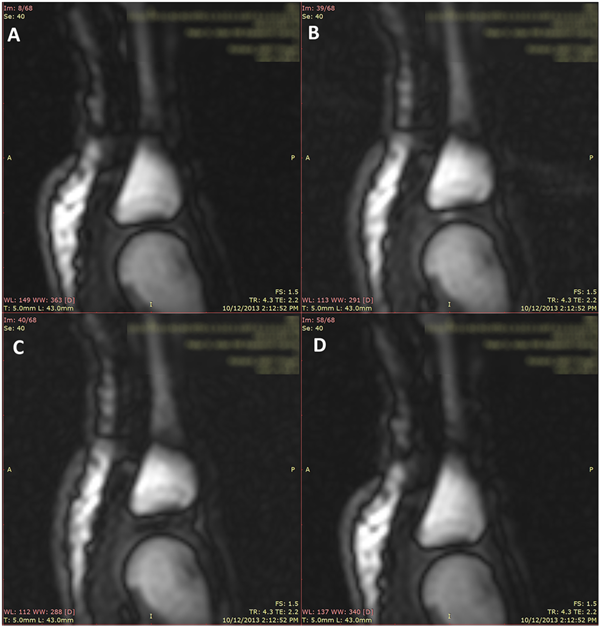

当然,也有一些不同的观点。2005 年加拿大的科研团队,动态核磁共振扫描手指关节,他们发现,在手指关节之间充满了滑液,当手指受到牵拉时,滑液也会做出相应变化,这个过程中,滑液中会有气体出现,并在滑液中形成气泡。直到手指发出咔的声音,这个气泡都会存在。因此,他们认为掰手指时响声的出现,并不是气泡破裂产生的,而是和关节内空腔形成有关。

关节牵开时,可以看到关节腔里面有黑颜色的空腔形成